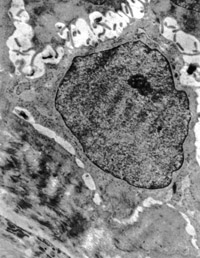

5-2-2 伤后第1天,毛细血管内皮细胞核固缩,管腔内血液凝集和瘀滞 TEM×6000